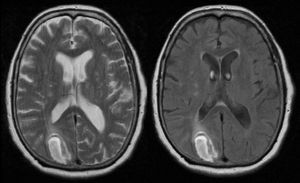

Case 2Our second patient, a 74-year-old man with a history of type 2 diabetes mellitus, came to our hospital due to sudden-onset inability to perceive anything on the left visual hemifield after experiencing a shock. The physical examination revealed left homonymous hemianopsia and mild left spatial neglect. He showed no sensory extinction; plantar reflexes were flexor bilaterally. His gait was cautious but showed no clear motor dysfunction. A brain CT scan revealed an acute haemorrhage in the right occipital area. A transcranial Doppler echo study showed that the contrast bolus reached the middle cerebral artery before the tenth beat, which was suggestive of dural fistula. A brain MRI scan revealed high signal intensity at the periphery of the lesion in T1-weighted sequences and a hyperintense lesion in T2-weighted and FLAIR sequences. Findings were compatible with an intraparenchymal haemorrhage in the right occipital cortical–subcortical area exerting a mass effect (Fig. 2).